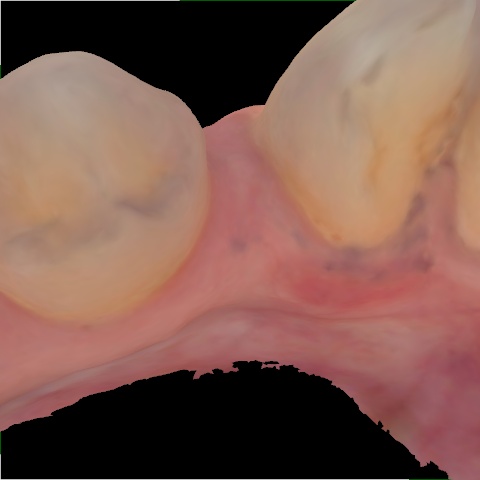

Incorrect Quality Level

The reference annotation for this image is

None

.

Please select the correct quality level.

Annotated as "Bad"